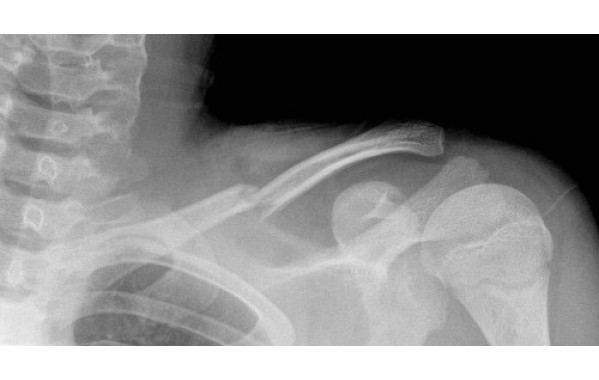

Перелом ключицы

Перелом ключицы  Диагностика перелома ключицы

Диагностика перелома ключицы

Перелом ключицы

Перелом ключицы  Диагностика перелома ключицы

Диагностика перелома ключицы